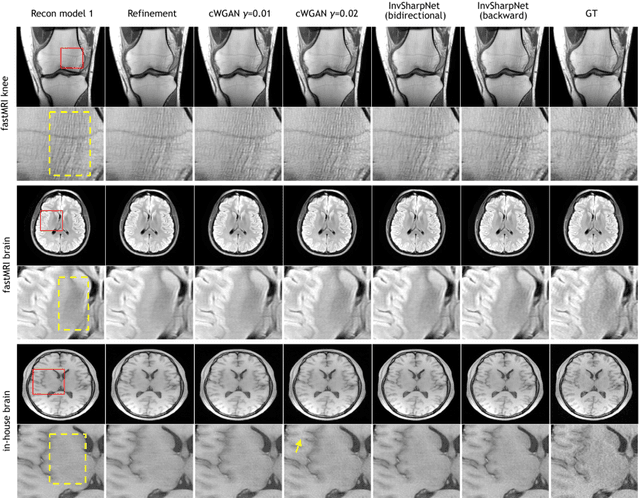

Abstract:High-quality MRI reconstruction plays a critical role in clinical applications. Deep learning-based methods have achieved promising results on MRI reconstruction. However, most state-of-the-art methods were designed to optimize the evaluation metrics commonly used for natural images, such as PSNR and SSIM, whereas the visual quality is not primarily pursued. Compared to the fully-sampled images, the reconstructed images are often blurry, where high-frequency features might not be sharp enough for confident clinical diagnosis. To this end, we propose an invertible sharpening network (InvSharpNet) to improve the visual quality of MRI reconstructions. During training, unlike the traditional methods that learn to map the input data to the ground truth, InvSharpNet adapts a backward training strategy that learns a blurring transform from the ground truth (fully-sampled image) to the input data (blurry reconstruction). During inference, the learned blurring transform can be inverted to a sharpening transform leveraging the network's invertibility. The experiments on various MRI datasets demonstrate that InvSharpNet can improve reconstruction sharpness with few artifacts. The results were also evaluated by radiologists, indicating better visual quality and diagnostic confidence of our proposed method.